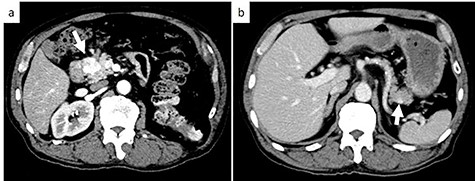

On examination, the patient had conjunctival pallor, blood pressure: 147/79 mmHg after transfusion and pulse: 95 beats per minute. Laboratory blood tests revealed a hemoglobin level at 7.8 g/dl. We decided to perform an emergency angiography which revealed a highly vascularized tumor at the pancreas head (Fig. 1a). The tumor was supplied with blood from a branch of the gastroduodenal artery. No extravasation of contrast medium was observed. Embolization of the anterior superior pancreatoduodenal artery and the right gastric epiploic artery was performed, and then also of the gastroduodenal artery, the right gastric epiploic artery, and the gastroduodenal artery. Angiography thereafter confirmed that all feeder arteries of the tumor had been embolized (Fig. 1b). Gastrointestinal hemorrhaging ceased after embolization. The patient did not complain of any abdominal pain after embolization and his medical condition was stable.

Emergency angiography; (a) emergency angiography showing the hypervascular tumor in the pancreas head (white arrow); (b) embolization of the gastroduodenal artery (white arrow).